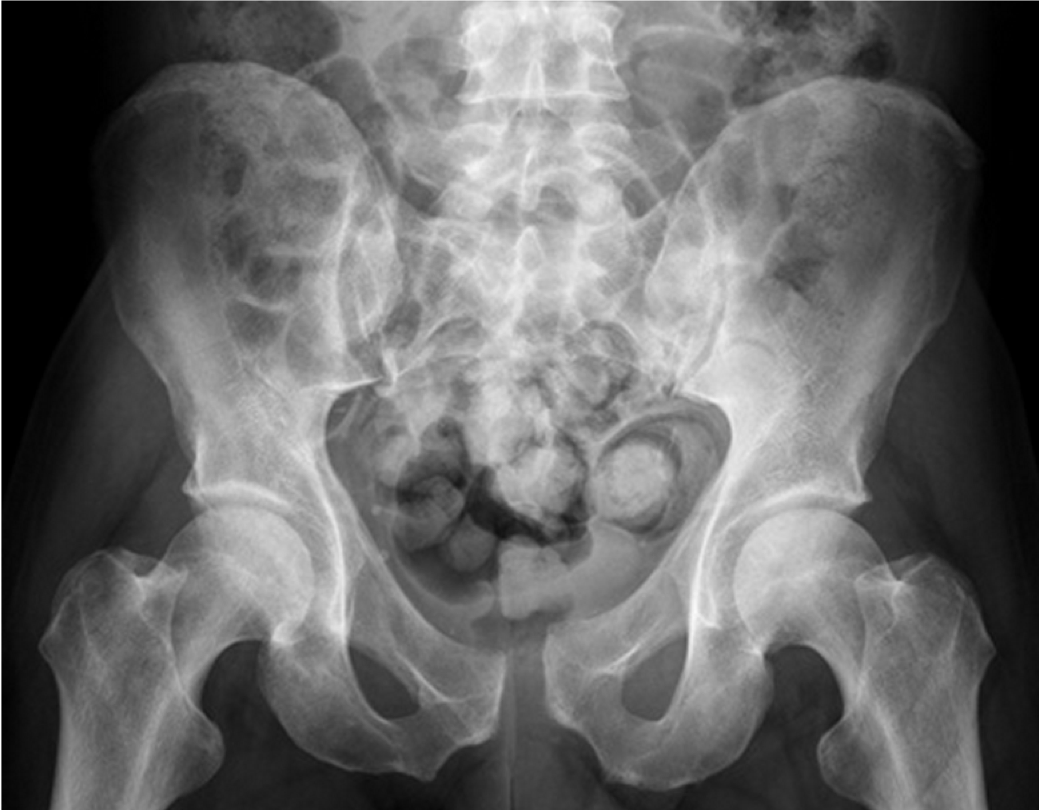

An 81 year old woman fell in her garden, and has pain in her right groin. Her right leg does not appear shortened or externally rotated. Her X-ray is shown.

What can you see?

What is meant by the ‘pubic ring’ and why is this important?